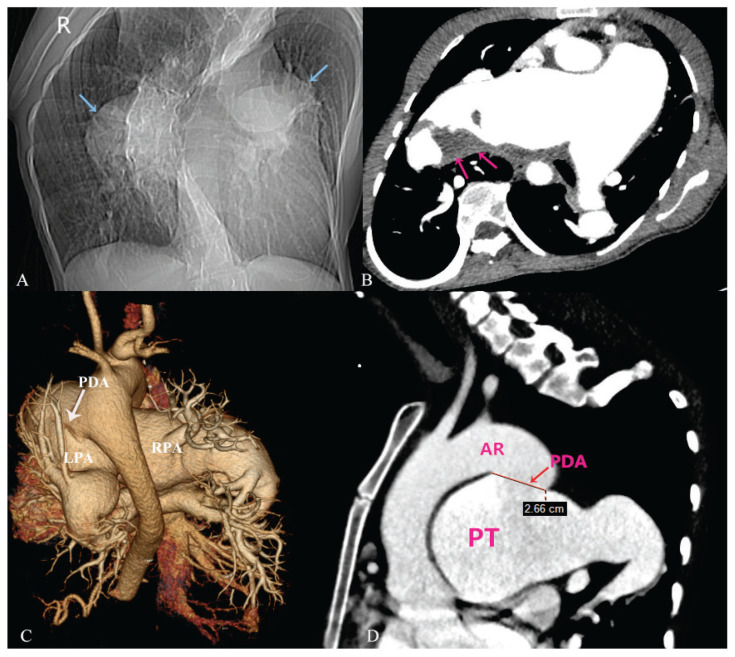

Hoarseness caused by aneurysmal central pulmonary artery secondary to a giant patent ductus arteriosus associated with Eisenmenger's syndrome.

{"title":"Hoarseness caused by aneurysmal central pulmonary artery secondary to a giant patent ductus arteriosus associated with Eisenmenger's syndrome.","authors":"Danling Luo, Xiaojun Xie","doi":"10.5603/cj.104216","DOIUrl":null,"url":null,"abstract":"","PeriodicalId":93923,"journal":{"name":"Cardiology journal","volume":"32 4","pages":"434-435"},"PeriodicalIF":0.0000,"publicationDate":"2025-01-01","publicationTypes":"Journal Article","fieldsOfStudy":null,"isOpenAccess":false,"openAccessPdf":"https://www.ncbi.nlm.nih.gov/pmc/articles/PMC12410943/pdf/","citationCount":"0","resultStr":null,"platform":"Semanticscholar","paperid":null,"PeriodicalName":"Cardiology journal","FirstCategoryId":"1085","ListUrlMain":"https://doi.org/10.5603/cj.104216","RegionNum":0,"RegionCategory":null,"ArticlePicture":[],"TitleCN":null,"AbstractTextCN":null,"PMCID":null,"EPubDate":"","PubModel":"","JCR":"","JCRName":"","Score":null,"Total":0}